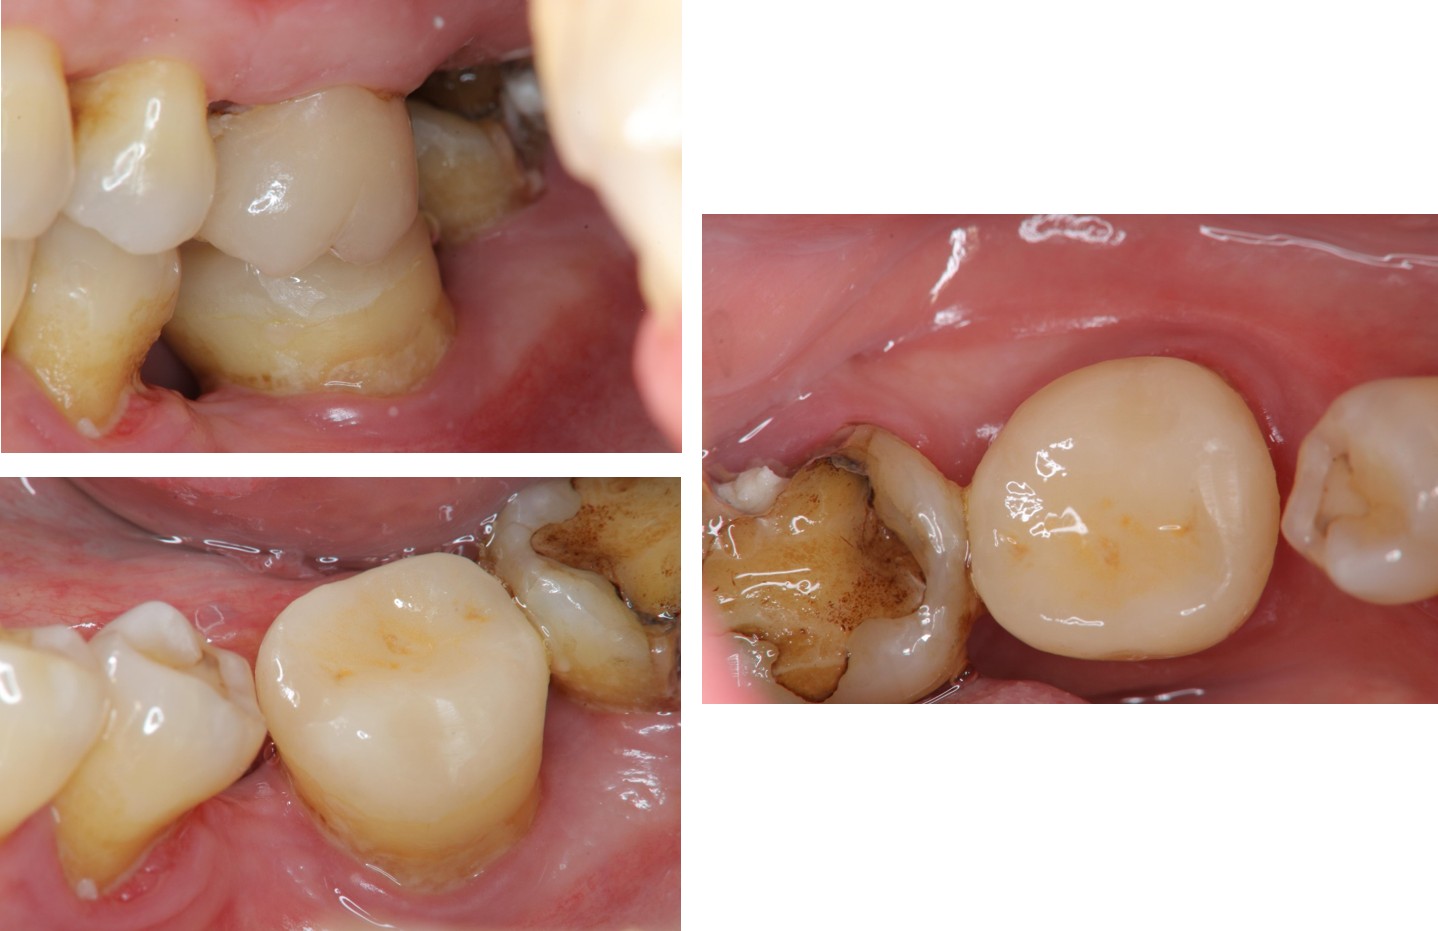

治療前,再次蛀牙,牙齒排列不整

蛀牙已至牙髓

治療後,功能與美觀恢復

術前、術後比較